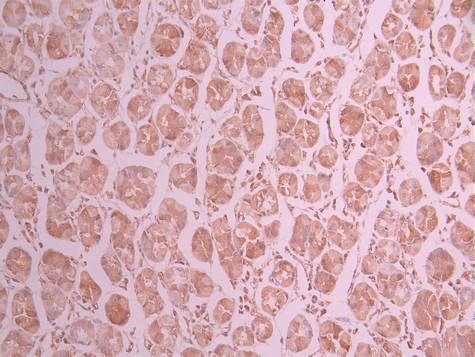

IHC image of CSB-RA266593A0HU diluted at 1:100 and staining in paraffin-embedded human breast cancer performed on a Leica BondTM system. After dewaxing and hydration, antigen retrieval was mediated by high pressure in a citrate buffer (pH 6.0). Section was blocked with 10% normal goat serum 30min at RT. Then primary antibody (1% BSA) was incubated at 4°C overnight. The primary is detected by a Goat anti-rabbit polymer IgG labeled by HRP and visualized using 0.05% DAB.